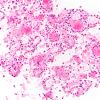

Meningitis

Meningitis, acute (2)